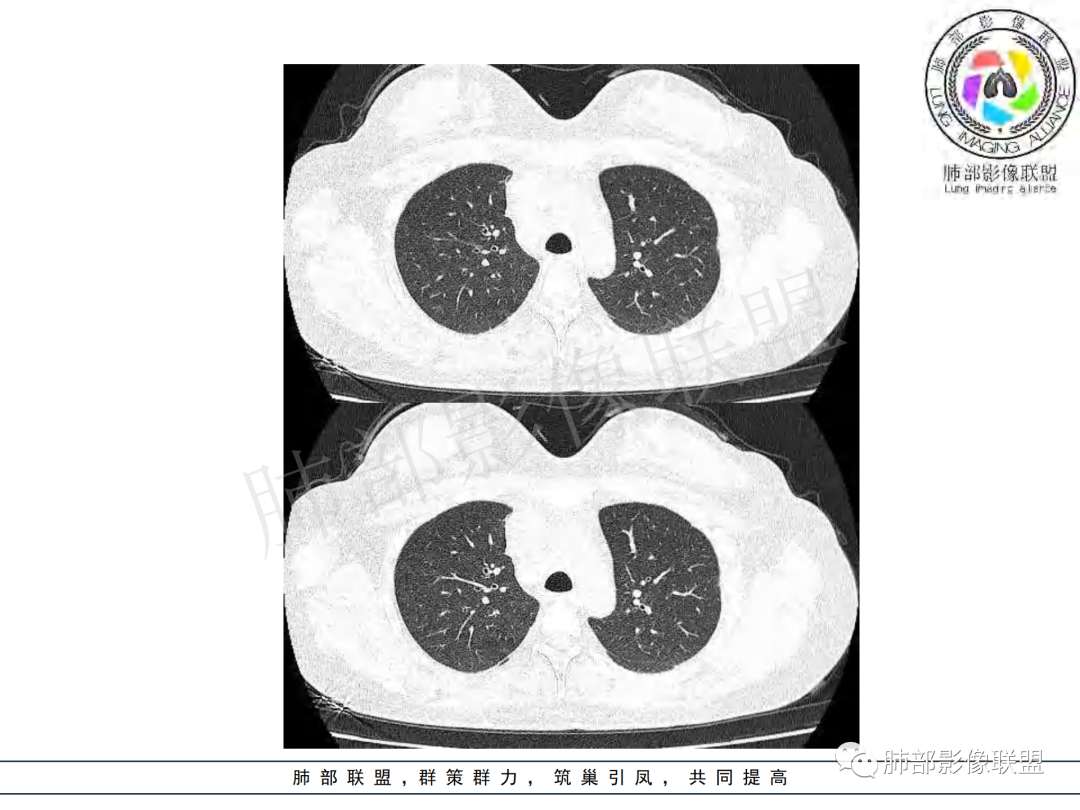

女,20,病程长达8月,发热、胸痛、右侧胸腔积液病史。胸部CT:右肺门旁不规则肿块影,右中间支气管腔内结节,纵隔多发淋巴结肿大;强化不均匀,灶性坏死灶,环形强化;右侧少量胸腔积液并局部肉芽肿样突起。年轻女性,长病程,多部位,考虑慢性炎症,结核?鉴别肿瘤。

支气管腔内有占位,肺门区病灶和胸膜结节明显强化,淋巴结环状强化为主,部分明显强化,年轻女性,首先考虑结核,鉴别腺癌

青年女性,发热、胸痛、右侧胸腔积液病史,病程8个月。曾多次抗炎后均有好转。CT:右肺门旁肿块影,双侧胸膜结节,纵隔多发淋巴结肿大,边缘模糊;增强渐进性明显强化,纵膈淋巴结较彻底坏死灶,边缘环形强化。考虑结核,鉴别恶性肿瘤。

女性,20岁。高热、畏寒。右肺上叶近肺门区不规则肿块,周围斑点、片小结节影伴肿大淋巴结,肿块包绕并突入右主支气管腔内,增强后肿块不均匀强化,淋巴结环形强化中心低密度,考虑结核。

纵隔肺门及两侧胸膜强化结节,支气管管腔不通畅。结核能解释临床及影像,就是强化有点猛,这个妖怪真不好说。恶性如类癌/高级别黏表/恶性间皮也要考虑。

本例患者,年轻女性,慢性病程,多次抗感染治疗效果不佳,实验室检查示白细胞及中性粒细胞不高,不支持普通细菌感染,虽然肺泡灌洗液X-Pert检测阴性,结合患者胸部CT结核感染亦不能排除,胸部CT主要表现为右侧肺门及纵隔淋巴结肿大,仔细观察不难发现右中间支气管内新生物凸向管腔内,增强扫描,右肺门(10R)及纵隔淋巴结(2R,4R)明显不均匀强化,内部呈不规则低密度无强化区,被周边高强化区包绕(环形强化)的特点,首先应当想到纵隔淋巴结结核诊断。淋巴结分布亦不符合肺部恶性肿瘤迁徙途径。